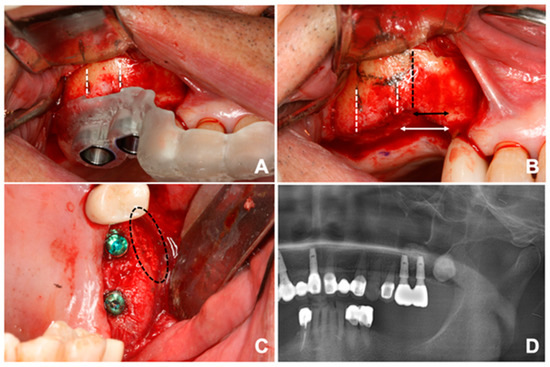

2.4. Surgical Procedure

3. Results